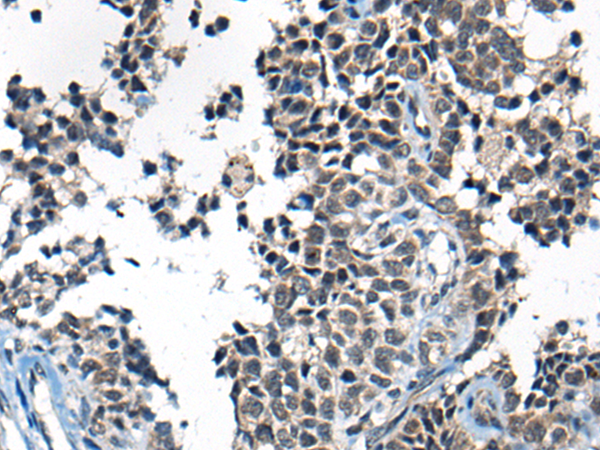

ELISA, IHC |

IHC positive control: |

Human ovarian cancer |

IHC Recommend dilution: |

25-100 |